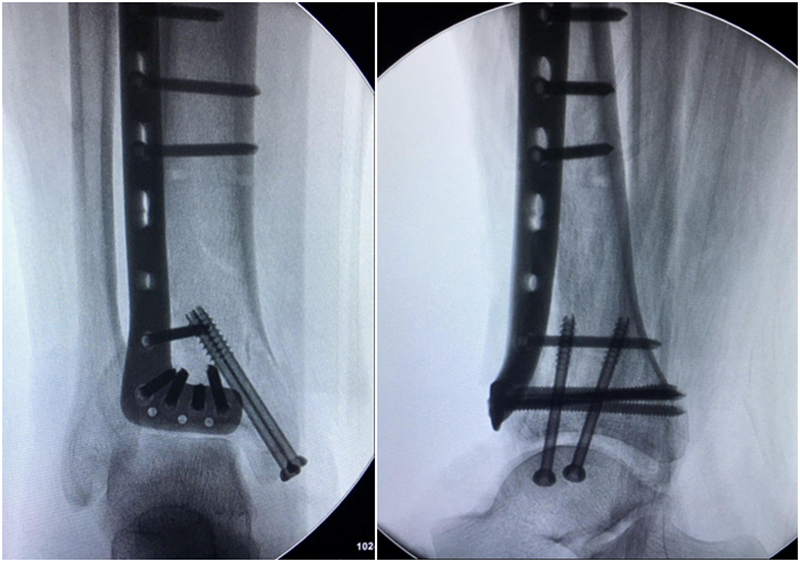

术中资料:切口与术中C-臂检测

图9 手术L切口远端横臂切口略偏近端,踝关节显露稍显不足,经延长“L”切口横臂后解决

图10 术中